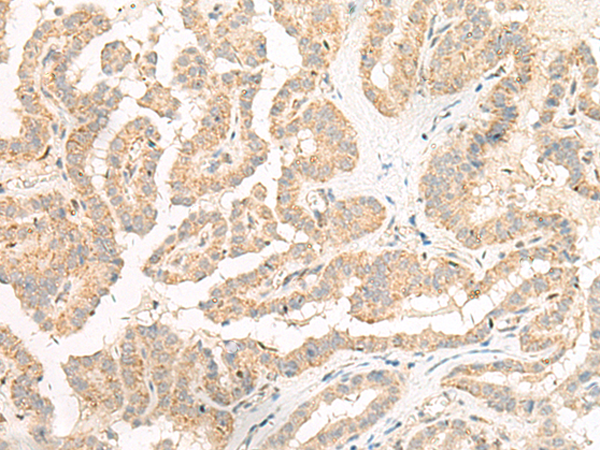

分类: 科研抗体货号: P06607别名: MTGM; MTGMP; C20orf52; bA353C18.2应用: WB,IHC反应种属: Human, Mouse